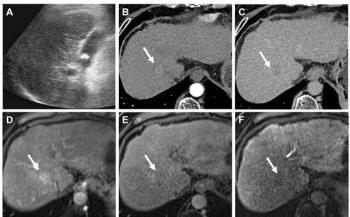

CT colonography also detects occult aortic aneurysmsNewsletter